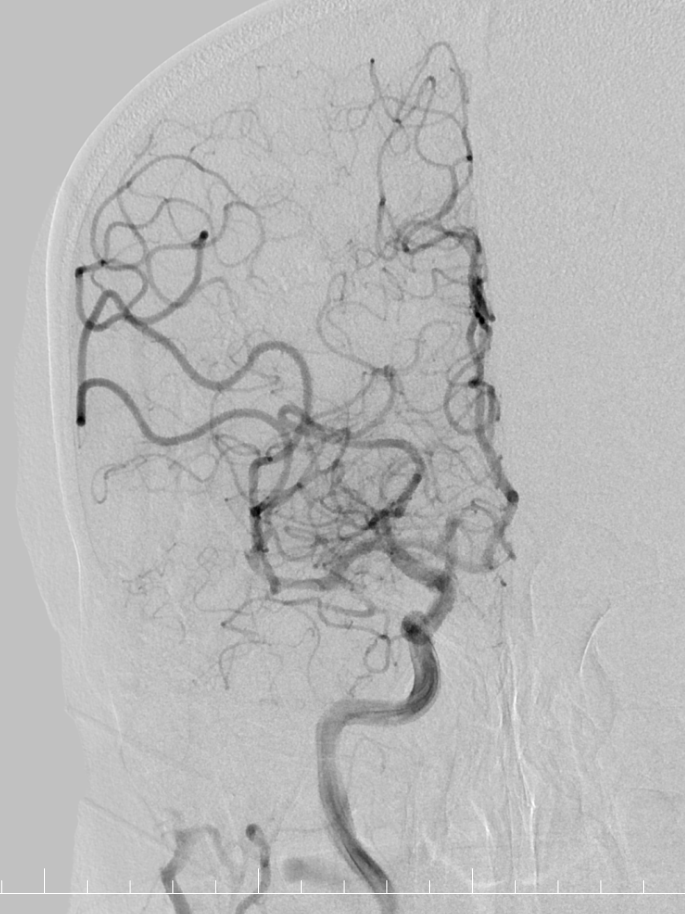

造影提示右侧大脑中动脉M2段下干闭塞。

动脉长鞘怎么置入有励可说|Locaste 088励楷长鞘及Tarvos微导丝在右侧大脑中动脉M2段取栓术中的应用_https://www.jmylbn.com_新闻资讯_第10张

动脉长鞘怎么置入有励可说|Locaste 088励楷长鞘及Tarvos微导丝在右侧大脑中动脉M2段取栓术中的应用_https://www.jmylbn.com_新闻资讯_第11张